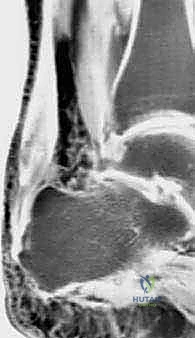

وتر أخيل ليس مجرد وتر عادي؛ إنه الكابل الحيوي الأقوى والأضخم في جسم الإنسان. يربط هذا الوتر الجبار عضلات الساق الخلفية (عضلة السمانة) بعظم الكعب، وهو المحرك الأساسي الذي يسمح لك بالوقوف على أطراف أصابعك، والمشي، والجري، والقفز. ولكن، عندما يتعرض هذا الوتر لإجهاد متكرر على مر السنين، أو نتيجة لعوامل بيولوجية وميكانيكية معينة، فإنه يبدأ في التآكل. تتدهور أليافه الكولاجينية القوية، وتتحول إلى نسيج ندبي ضعيف ومؤلم، وتزداد سماكته بشكل مرضي، مما يجعله ليس فقط مصدر ألم دائم، بل يجعله قنبلة موقوتة معرضة للتمزق الكامل في أي لحظة.

3. استئصال الأنسجة التالفة (Debridement)

هذه خطوة حاسمة. يتم فتح الغلاف المحيط بوتر أخيل وفحص الوتر بدقة. يقوم الجراح بإزالة جميع الأنسجة الندبية، الميتة، والمتكلسة (التي تسبب الألم). في الحالات الشديدة، قد يتم إزالة أكثر من 50% من حجم وتر أخيل الأصلي لأنه لم يعد صالحاً للعمل.